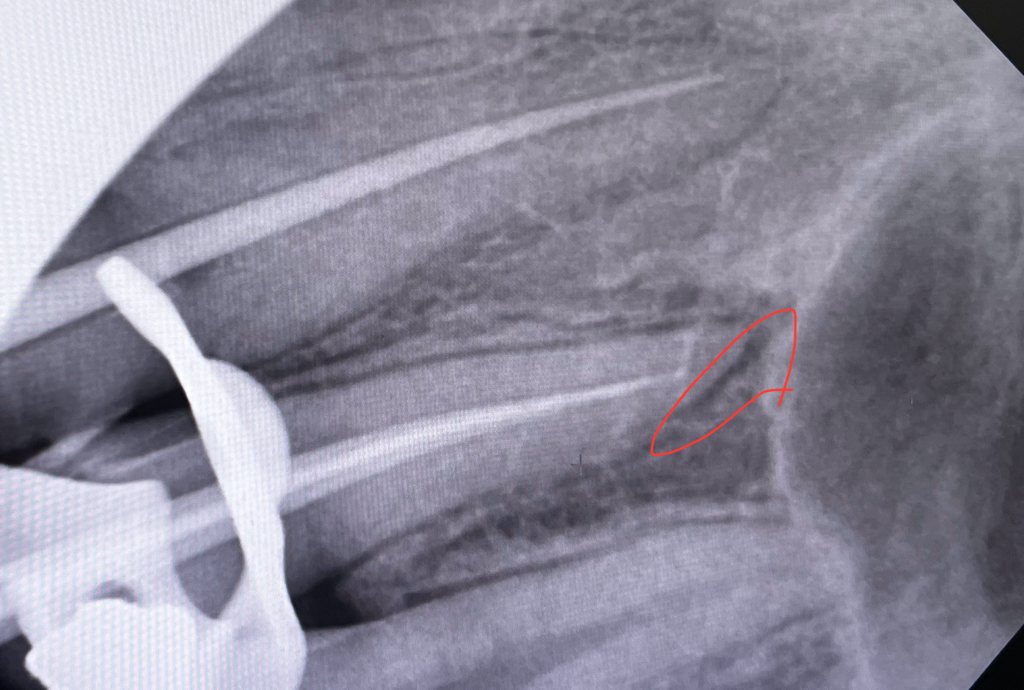

(X-Ray 사진 첨부) 충치균이 치아를 넘어 잇몸 뼈까지 부식시켰다고 합니다

왼쪽 위 어금니와 앞니 사이 치아에 충치가 심해 신경치료를 진행하는 중 x선 사진을 촬영하여 충치균이 치아를 넘어 잇몸 뼈까지 부식시킨 상태라고 의사가 말하였습니다. 그리고 이러한 경우 예후가 좋지 않을 가능성이 높다고 말하였습니다.

사진에 표시한건 치아 뿌리끝에 염증이 생겨서 그렇게 보이는겁니다. 신경치료를 해서 염증을 제거하시면될것같습니다.

잇몸뼈로 염증이 파급되었기 때문에 처음에 신경치료를 시작한 것이고 신경치료 후 증상이 점차 개선되면 크라운을 씌웁니다